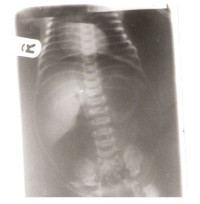

Necrotizing enterocolitis (NEC) is a disease of premature infants. Following clinical diagnosis, there is need for early radiological evaluation for confirmation and identification of complications. ensures early initiation of appropriate steps of management which will reduce the mortality associated with the disease. This paper describes a series of 3 cases of NEC and emphasizes early radiological evaluation of these patients with the various imaging modalities available, to cut down on the disease burden in our environment.